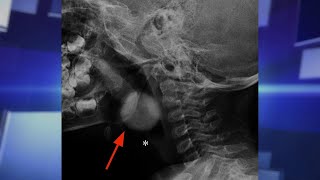

YouTube Excerpt: Overview: A new study shows that injuries involving shopping carts have increased 30% in the last two decades. Dr. Gary Smith of ...